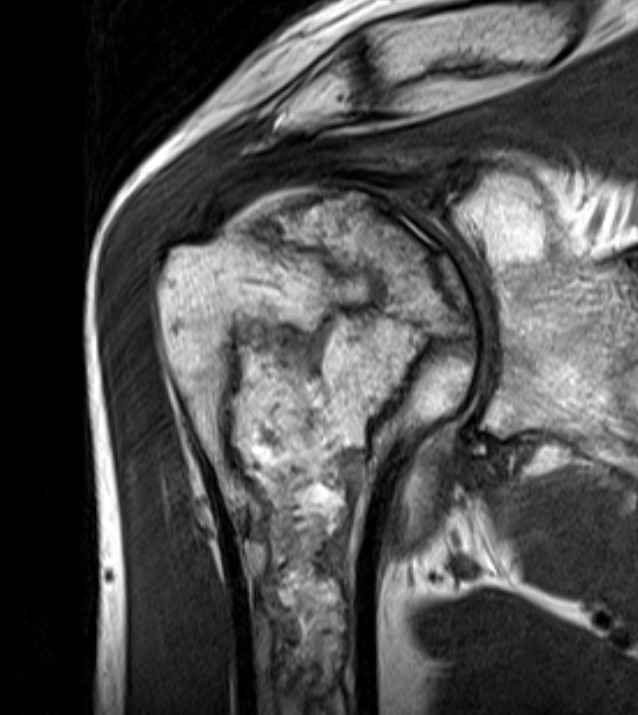

MRI

- key feature central signal same as cancellous bone (intermediate) on both T1 and T2

- rim enhances on both T1 and T2 with contrast

- can be centrally enhancing in acute setting on T2